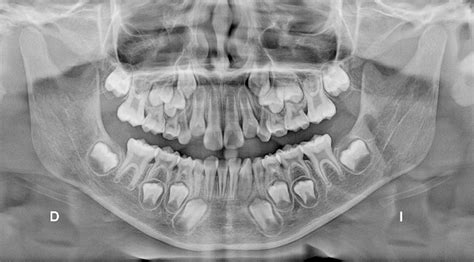

¿Por qué mi hijo tiene “dos filas” de dientes?

La aparición de una doble fila de dientes es habitual en niños. Sin embargo, los padres deben asegurarse que el proceso de la erupción de los dientes definitivos no representará un futuro problema en la salud bucodental de los mismos. Por lo tanto, en cuanto observen la aparición de dos filas de dientes en alguno de sus hijos, deberán pedir cita con su dentista infantil y juvenil.

En ocasiones, recibimos familias en la clínica odontopediátrica preguntando sobre las dos filas de dientes de su hijo. Esto es observado por los padres con frecuencia cuando los incisivos inferiores permanentes erupcionan sin que se hayan caído todavía los incisivos temporales.

Dientes de Tiburón

Para que caiga un diente temporal, es imprescindible que su raíz se haya reabsorbido. Si el definitivo no erupciona justo debajo del diente de leche, sino desviado de su trayectoria y posición idóneas (generalmente por detrás del diente temporal), aparecerá en boca, creando la sensación de dos filas de dientes. Por lo tanto, el diente de leche seguirá estando presente porque su raíz no se ha reabsorbido. Esto es lo que da el aspecto de que el niño tiene una “doble fila de dientes” o lo que se conoce como “dientes de tiburón”.

Sin embargo, también es común que con el empuje de la lengua los incisivos definitivos se desplacen al lugar que les corresponde. Por tanto, poco a poco reabsorban las raíces de los de leche, que se moverán cada vez más y terminarán por caerse, eliminando el problema de la doble fila de dientes o dientes montados. Este proceso, que puede parecer algo lento y suele suceder en el transcurso de varias semanas.

Este problema de dos filas de dientes debe ser estudiado por un odontopediatra para decidir si tomar una conducta expectante o extraer el diente temporal. El profesional debe decidir en cada caso lo más conveniente para el niño o adolescente. Además, los padres también serán aconsejados teniendo en cuenta el aspecto oral del menor.

Dientes Gemelos

En ocasiones aparecen una doble fila de dientes porque desde un germen dentario único se forman dos dientes equivalentes. Esta fusión dental desde este germen dentario único también se denomina “dientes gemelos”. Este caso puede ocurrir, o bien, entre dos dientes normales, o bien, entre un diente normal y otro supernumerario, aunque en este segundo caso es difícil diferenciar entre la fusión y la geminación dental.